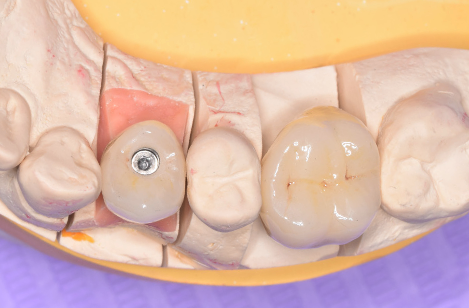

După câteva zile, coroana ajunge în cabinetul de medicină dentară pe un model realizat din gips sau printat la o imprimantă 3D care reproduce dinții pacientului. (Fig. 3.5.9 și 3.5.10)